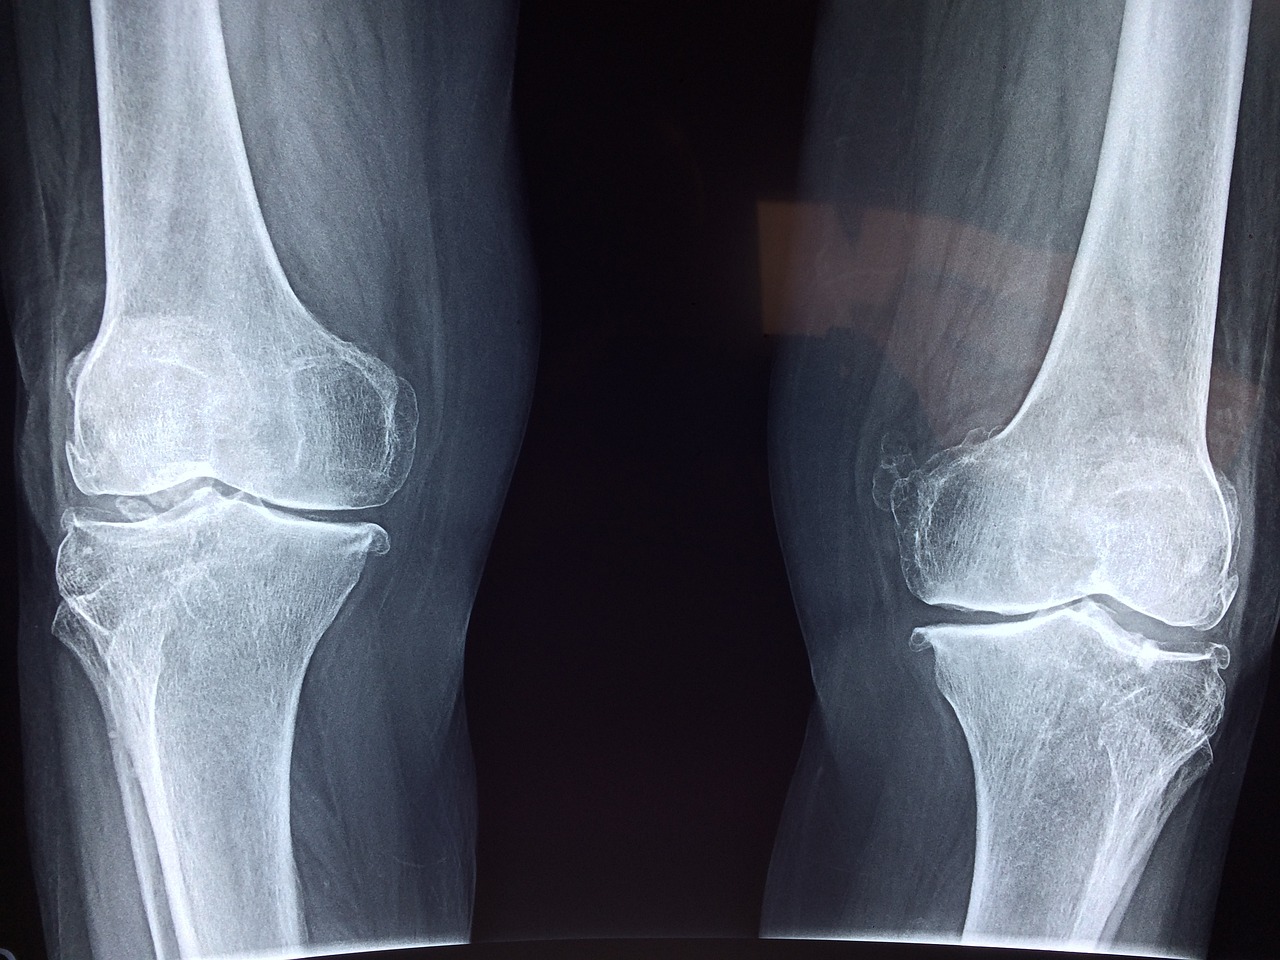

오늘은 무릎 연골 손상 증상에 대하여 알아보고, 무릎 연골주사 등 여러 치료법에 대해서도 알아보도록 하겠습니다.

무릎 연골 손상 증상

무릎 연골 손상시 치료방법

검진을 통해 무릎 연골이 손상된 것을 확인했다면 보존적 치료인 ✅약물 치료 ✅주사 치료 ✅ 물리 치료 등으로 치료하지만 이보다 심할 경우에는 수술이 불가피할 수도 있습니다.

관절 내시경 수술을 통해 절개 후 내시경과 수술 기구를 통해 직접 무릎을 확인하면서 시행하는 수술을 진행할 수도 있는데요 이럴 경우 3~5일가량 회복 기간이 필요합니다.

무릎 연골 주사는?

무릎 관절에 연골과 비슷한 히알루론산을 주입하는 주사입니다. 초기 관절염인 분들이 이러한 무릎 연골 주사를 이따금씩 맞으시는데요 6개월 간격으로 1주일에 3번가량 맞아야 금액 처리가 되는 점 참고하시기 바랍니다.

나이가 들 수록 무릎 연골에도 마모가 오기 때문에 이러한 주사를 통해 염증과 통증을 덜어주는 역할을 하는 것 입니다. 움직임이 부드러워지고 충격이 흡수되기 때문에 초반에는 아플 수 있으나 시간이 지나게 되면 스며들게 됩니다.